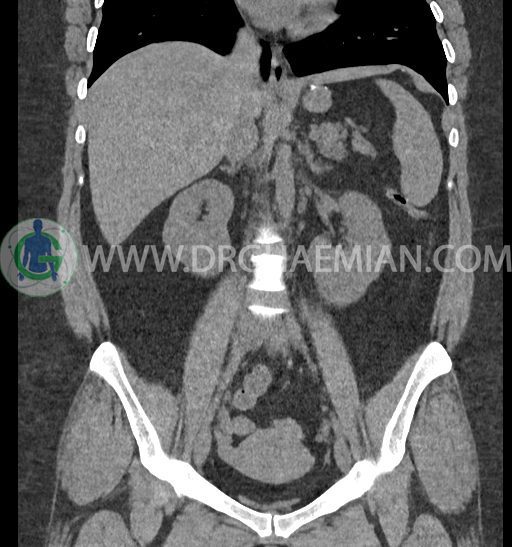

سی تی اسکن شکم و لگن با استفاده از اشعات ایکس تصاویر عرضی از ناحیه شکم و لگن ایجاد میکند. در این کیس کلیه نعل اسبی و سنگ کلیه مشاهده می شود.

در سی تی اسکن اسپیرال شکم و لگن بدون کنتراست (مولتی دیدکتور 16 با مقاطع ظریف و بازسازی های ساژیتال و کرونال) :

-horseshoe kidney

-حداقل سه سنگ 5mm در کلیه راست و یک سنگ 3mm در کلیه چپ بدون شواهدی از هیدرونفروز

-شواهد جراحی اسلیو قبلی در Body و فوندوس معده

-آپاندیس نرمال بصورت رتروسکال

مشهود است.